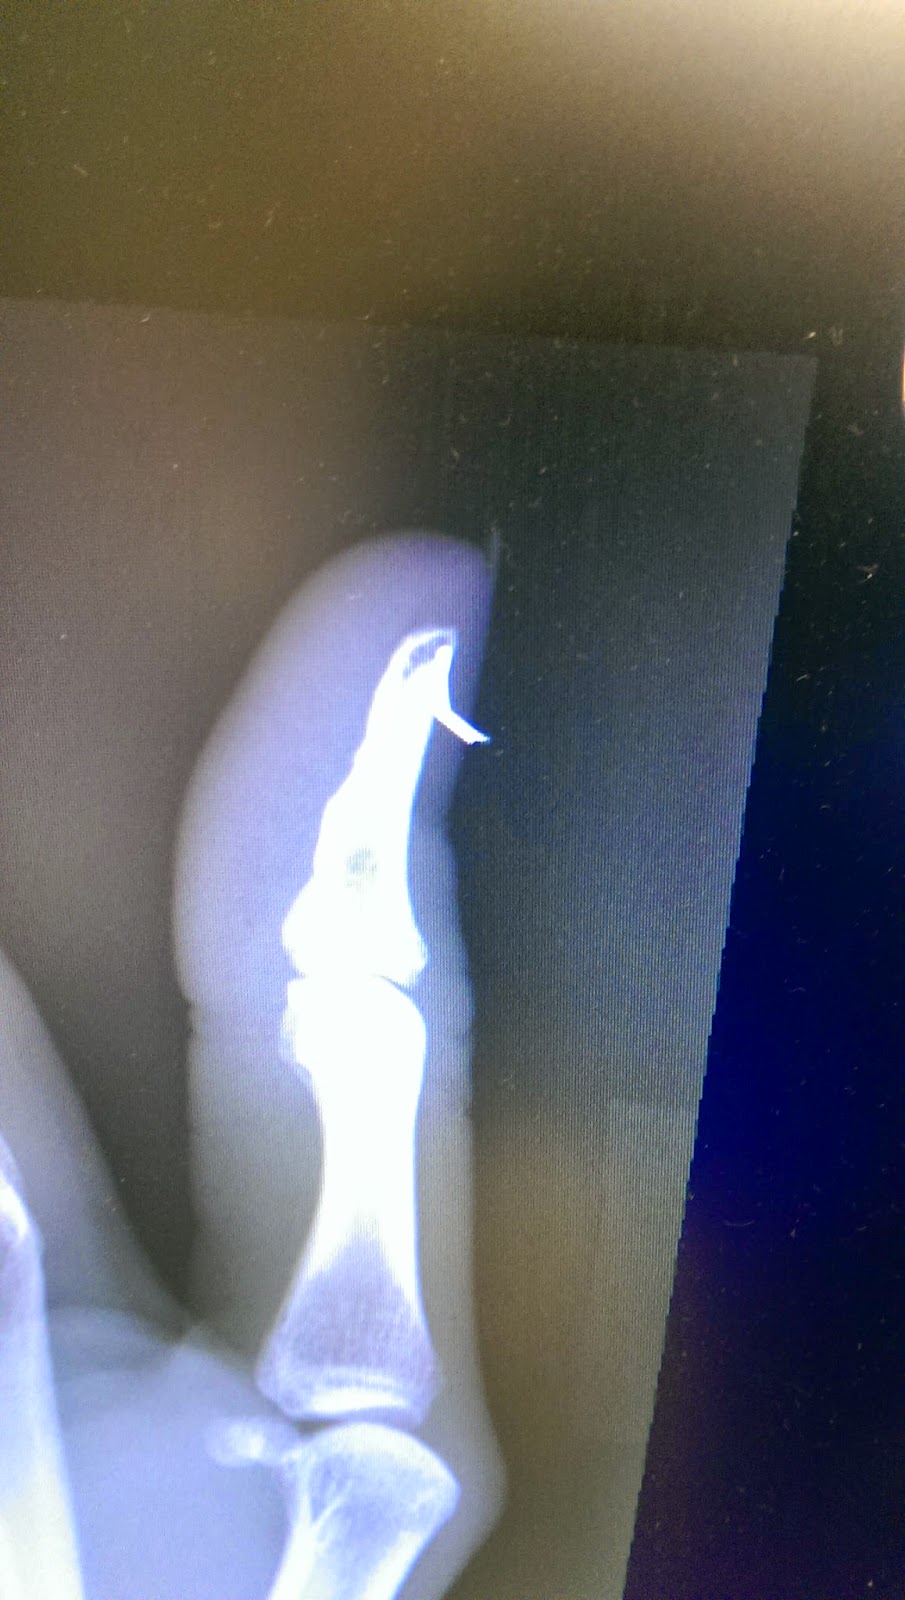

| x-ray showing the piece at a 90 degree angle |

And then I woke up feeling like I had just had the most amazing nap in the world. My thumb was completely numb and I was feeling really good. They wheeled me back into the room with a great big smile on my face. I finally got to eat after a day of fasting. After a few more nurse checks, I was good to go home. Apparently during the surgery they removed my nail and then did another x-ray. The needle had entered the nail, hit the bone, bent off of that and exited out the other side of my nail. There was still a small piece of needle in the bone but the dr decided it was better to leave it there.